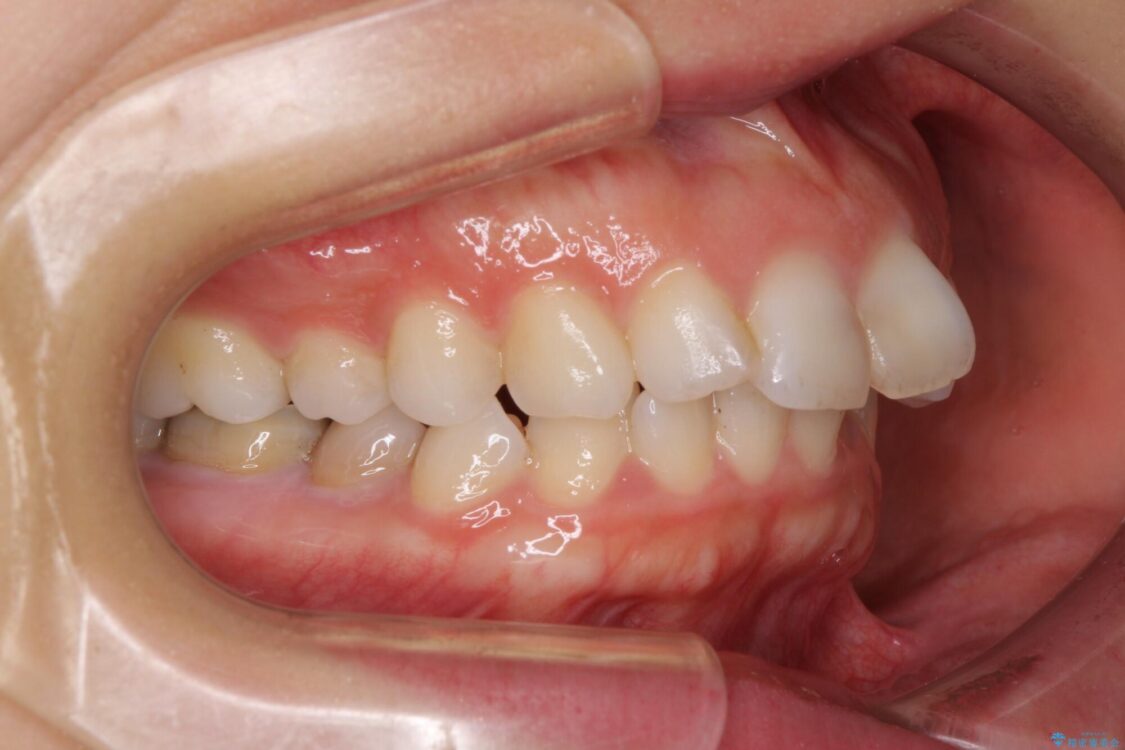

治療後

• 【モニター】出っ歯と咬み合わせを改善 ワイヤー装置の抜歯矯正 治療後画像

治療後について

奥歯の咬み合わせ改善には1年ほどの期間と処置中の噛みにくさを強いることとなりましたが、抜歯後はスムーズに治療を完了させることができました。

歯ぎしりの際に奥歯が干渉していた咬み合わせも理想的な状態に改善できました。